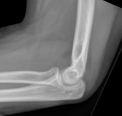

Die Befunde können recht unauffällig sein, und der einzige Anhaltspunkt kann das Fettpolsterzeichen sein (dreieckige, röntgenstrahlendurchlässige Schatten anterior und posterior des distalen Humerus auf dem seitlichen Röntgenbild, die auf eine Hämarthrose und eine Verlagerung des intraartikulären Fettpolsters hinweisen - häufig in Verbindung mit einer intraartikulären Skelettverletzung).

Bild des Ellenbogenfettpolsterzeichens (Hellerhoff (eigenes Werk), via Wikimedia Commons):

Ellenbogen Fettpolster Zeichen

James Heilman, MD, CC BY-SA 4.0, über Wikimedia Commons